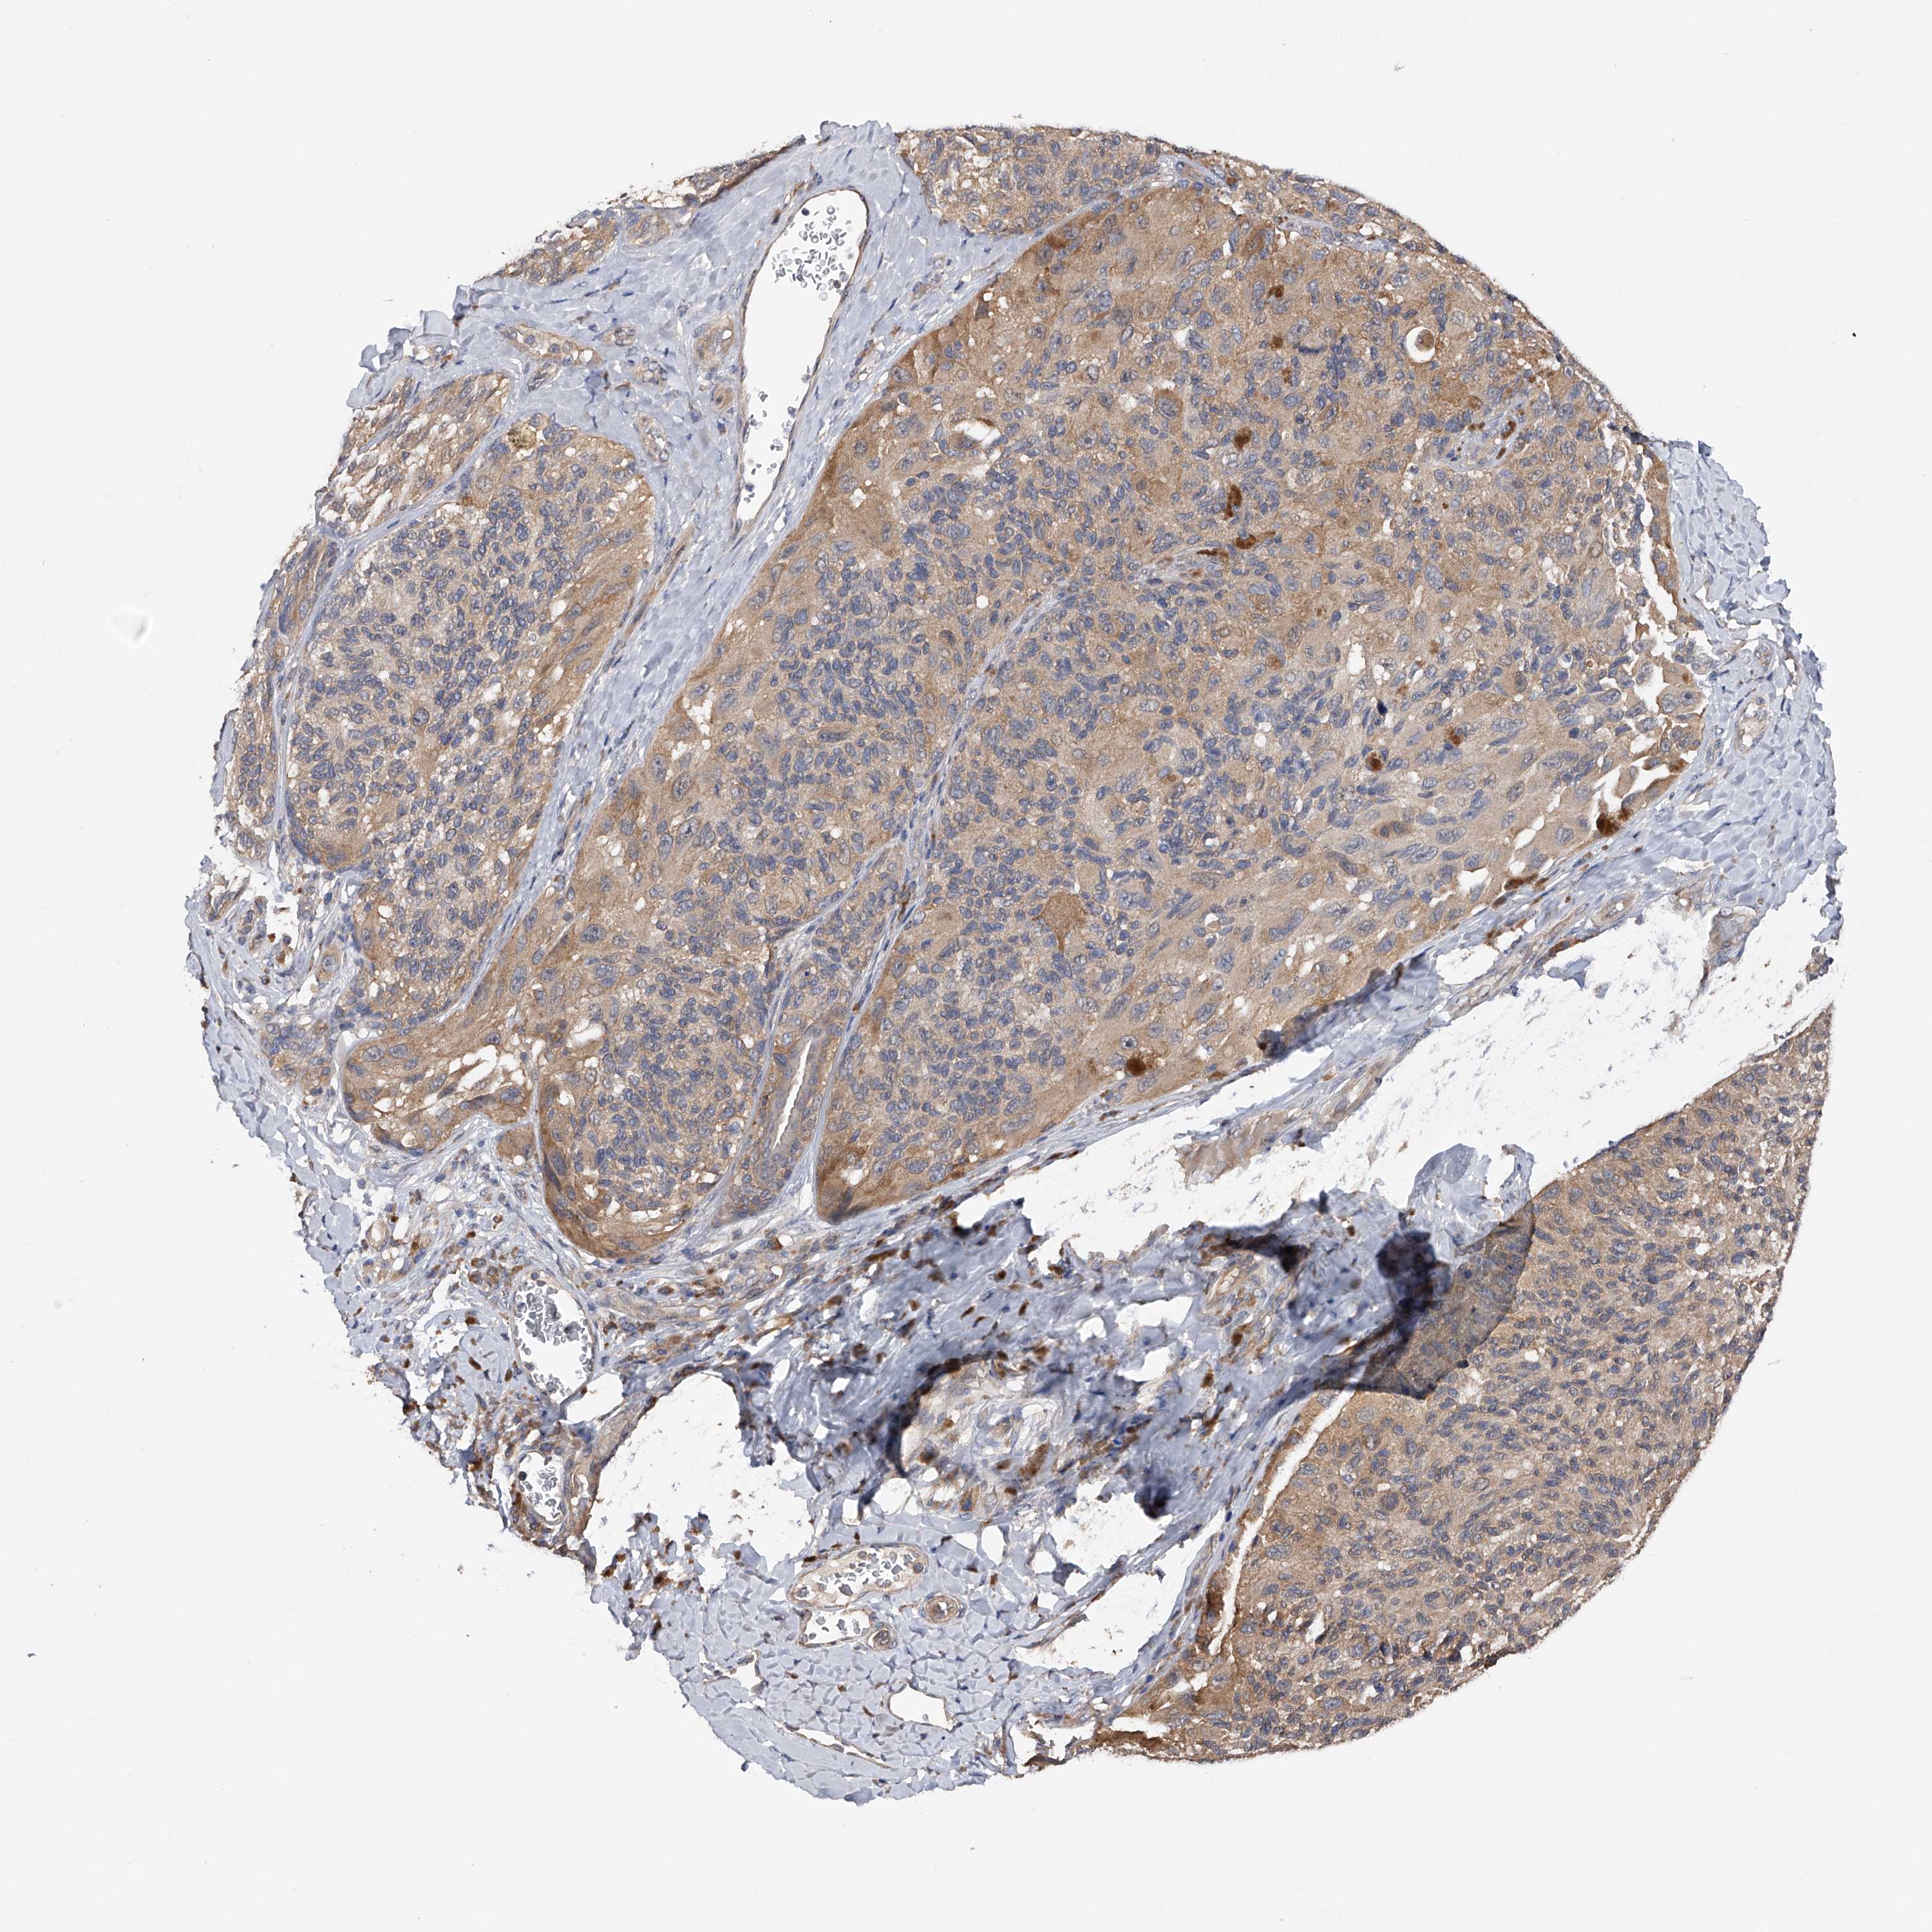

MELANOMA - Protein expressioni

A mouse-over function shows sample information and annotation data. Click on an image to view it in a full screen mode. Samples can be filtered based on level of antibody staining by selecting one or several of the following categories: high, medium, low and not detected. The assay and annotation is described here.

Note that samples used for immunohistochemistry by the Human Protein Atlas do not correspond to samples in the TCGA dataset.

Antibody stainingi

Antibody staining in the annotated cell types in the current human tissue is reported as not detected, low, medium, or high, based on conventional immunohistochemistry profiling in selected tissues. This score is based on the combination of the staining intensity and fraction of stained cells.

Each image is clickable and will lead to virtual microscopy that enables deeper exploration of all samples and also displays staining intensity scores, fraction scores and subcellular localization as well as patient and tissue information for each sample.

Antibody HPA018453

Antibody HPA019055

Antibody HPA028849

Antibody CAB034170

Malignant melanoma, NOS

Malignant melanoma, Metastatic site